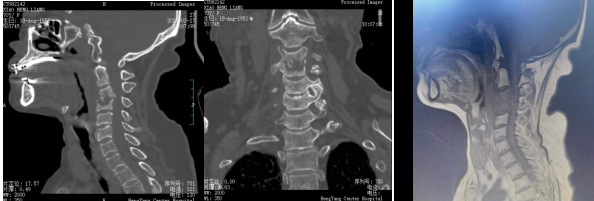

術(shù)前影像:C3、4椎體病變,椎管狹窄

患者入院后完善相關(guān)檢查,不查不知道,一查不簡單:患者頸椎疼痛不是簡單的肌肉勞損,而是頸椎骨頭出現(xiàn)了破壞、塌陷,神經(jīng)受壓。由于患者頸椎病變位置較高,骨質(zhì)破壞范圍較大,并后凸、脊髓受壓,椎體穩(wěn)定性差,稍有不慎容易出現(xiàn)災(zāi)難性后果?,F(xiàn)有的重建材料難以達(dá)到好的臨床效果,蘇光輝主任團(tuán)隊(duì)采用先進(jìn)的3D打印技術(shù),為患者進(jìn)行了個(gè)性化手術(shù)方案及假體設(shè)計(jì),假體與需要切除骨質(zhì)完美匹配,最大程度恢復(fù)解剖結(jié)構(gòu)及重建的穩(wěn)定性,對(duì)假體進(jìn)行骨小梁結(jié)構(gòu)設(shè)計(jì),具有良好的骨長入效果,能夠減少假體下沉及松脫等術(shù)后并發(fā)癥的發(fā)生。